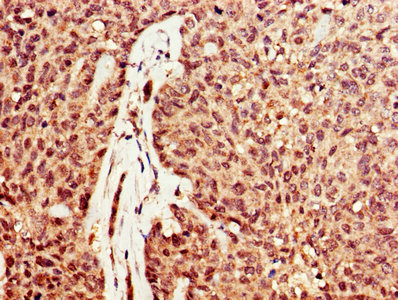

• IHC image of CSB-PA007049LA01HU diluted at 1:600 and staining in paraffin-embedded human ovarian cancer performed on a Leica BondTM system. After dewaxing and hydration, antigen retrieval was mediated by high pressure in a citrate buffer (pH 6.0). Section was blocked with 10% normal goat serum 30min at RT. Then primary antibody (1% BSA) was incubated at 4°C overnight. The primary is detected by a biotinylated secondary antibody and visualized using an HRP conjugated SP system.